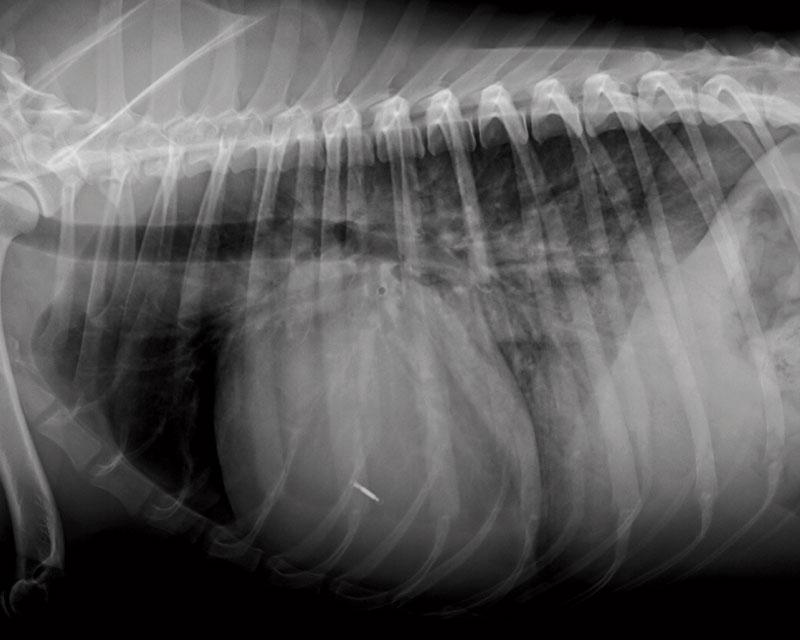

Figure 1a. Lateral radiograph of a dog with generalised cardiomegaly, vessel enlargement and diffuse lung opacity, particularly in the more caudal and ventral lung fields where air bronchograms are visible. These radiographic signs suggest heart disease and cardiogenic pulmonary oedema.

Thoracic radiography is a readily available confirmatory test and usually shows cardiomegaly, venous congestion and pleural effusion or pulmonary oedema3 (Figure 1).